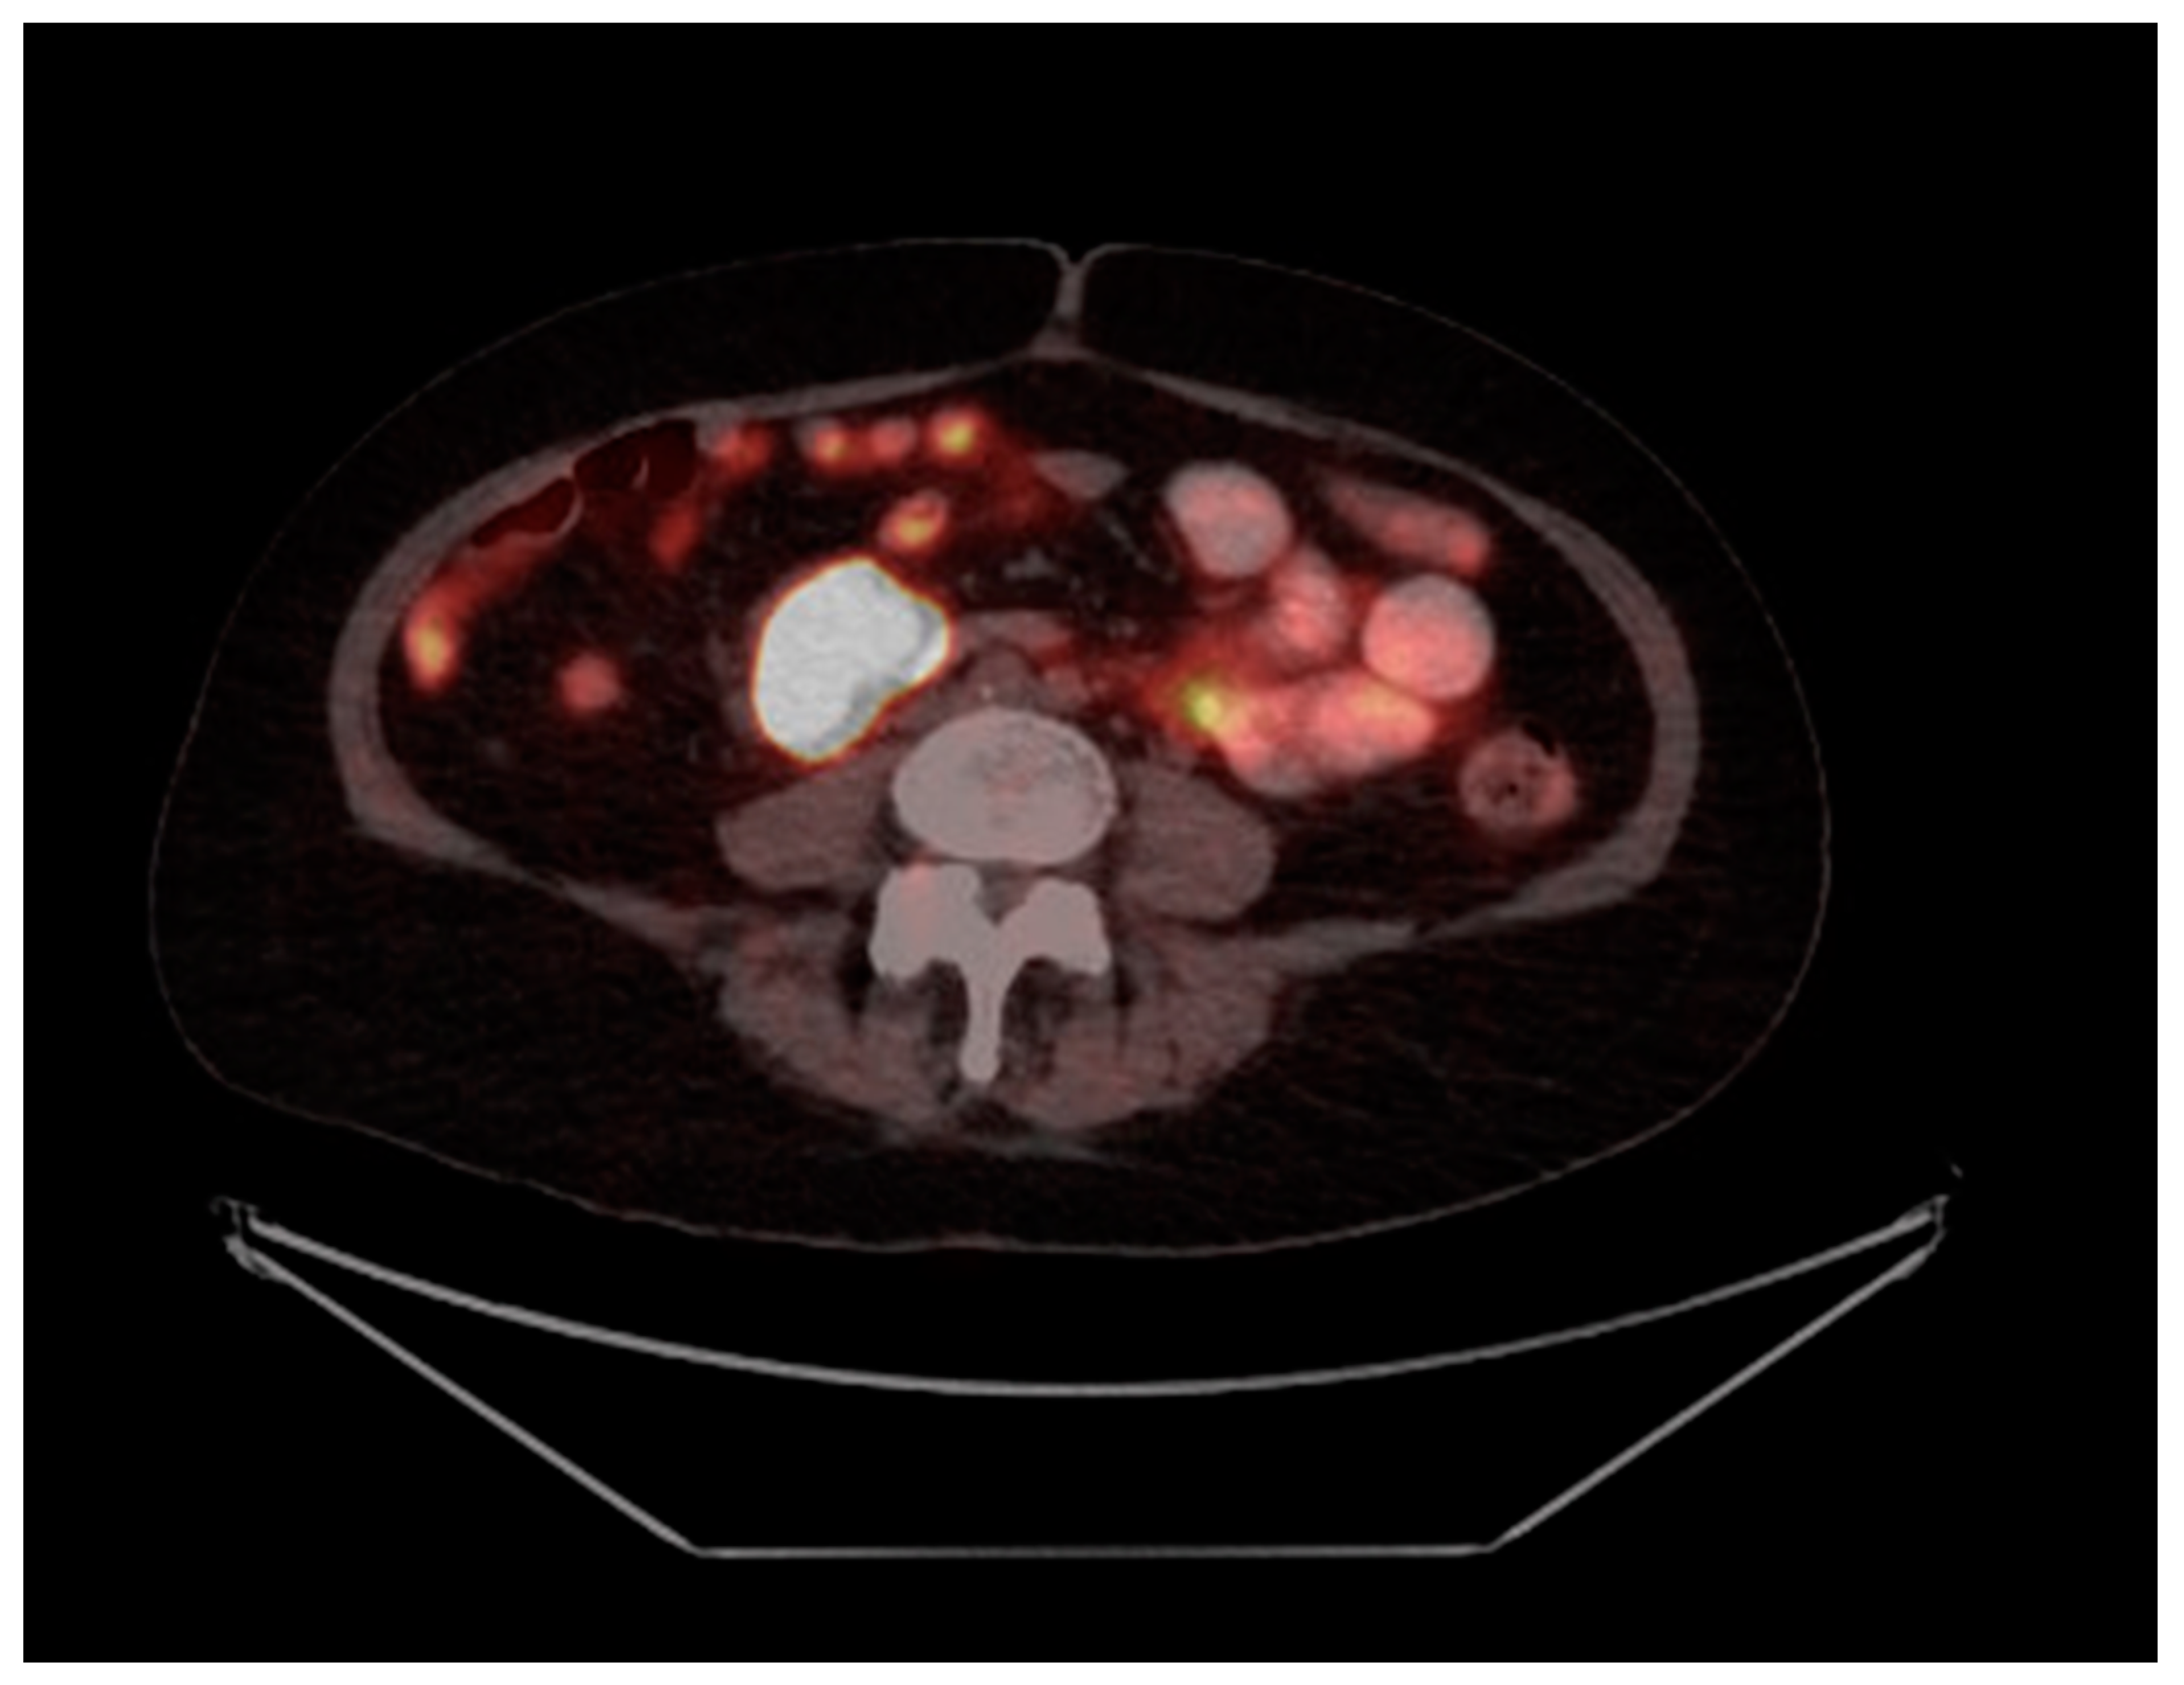

A Case of Cushing’s Syndrome from Well-Differentiated Neuroendocrine Tumors of the Small Bowel and Its Mesentery

2. Case Presentation